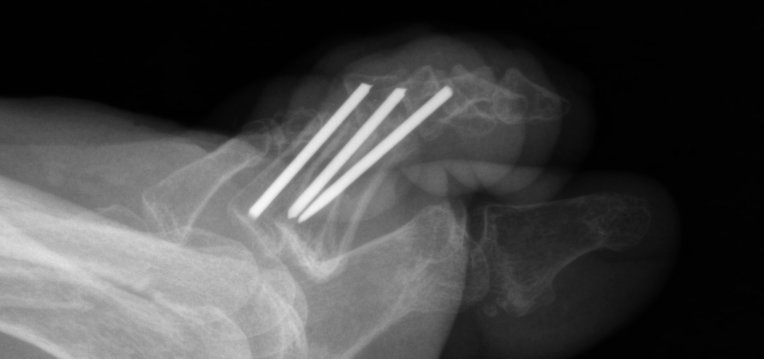

Implant sizing is important to avoid complications. Many of the newer hammertoe implants feature expanding “memory” metals, which not only aid in arthrodesis compression but also lend stability by expanding within the intramedullary canal. When using screws or K-wires, the surgeon must ensure that the diameter of the implant is appropriate for the diameter of the phalangeal intramedullary canals. Otherwise, rotation or residual flexion can occur as one can see in the photo above. In this example, the diameter of the embedded K-wires was too small and allowed for flexion and toggling within the intramedullary canal as well as loss of correction.

Furthermore, poor patient adherence can be detrimental to any procedure and contribute to hardware breakage and procedure failure. The left photo shows a foot two weeks after the patient had a well positioned and fixated proximal interphalangeal arthrodesis. However, by the four-week follow-up, the patient had returned to regular shoes against medical advice and returned to full duty at his job as a construction worker, contributing to implant failure.